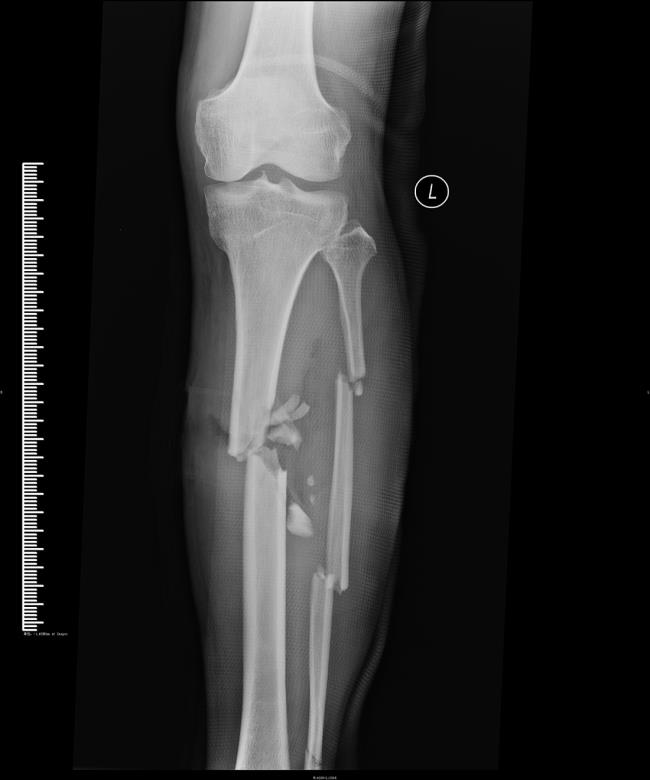

医药联合外固架肢体延长技术